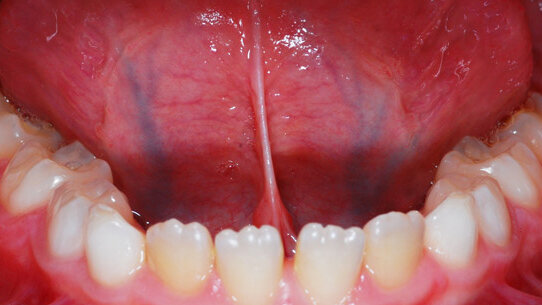

Il grado più grave di tale condizione si chiama anchiloglossia, detta anche “lingua legata” (tongue-tie), in quanto essa risulta totalmente fissata al pavimento della cavità orale e alla mucosa alveolare del lato linguale, rendendo così possibili solo i movimenti delle parti laterali della lingua stessa (Fig. 1).